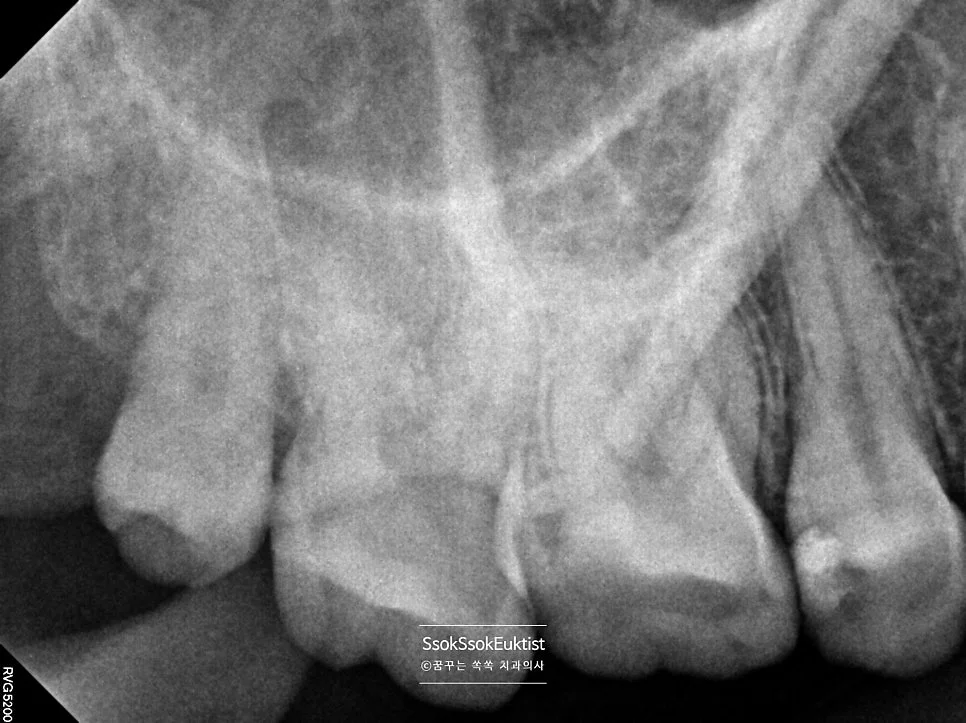

치아 사이를 가장 잘 볼 수 있는 교익 방사선(Bitewing X-ray) 사진을 통해 정확한 충치 진단을 시도합니다.

교익 방사선 사진을 촬영하였을 때, 치아의 가장 바깥 흰색 재질(법랑질)과 안쪽 회색 재질(상아질)을 나누는 선이 검은 음영으로 끊긴 느낌이면 충치로 진단합니다!

(위 사진에서 파란색 화살표로 표시된 부분)